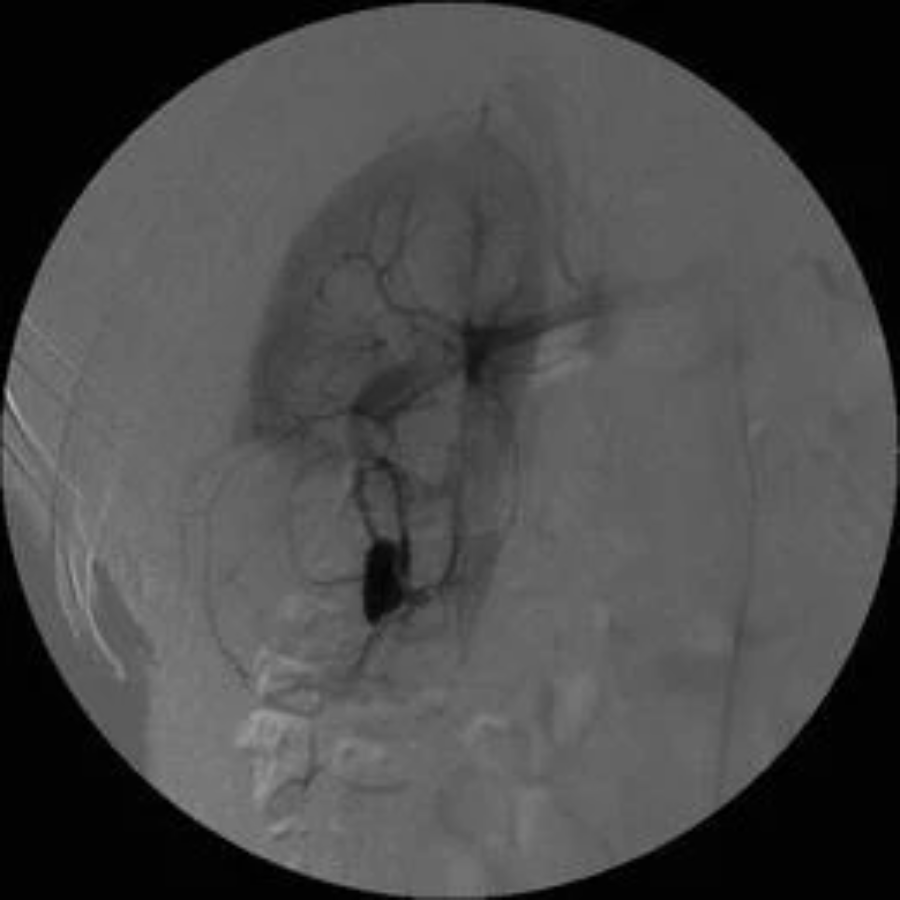

出血可发生于肾实质(肾小道)或盆腔内的损伤(漏斗部或盆腔撕裂)。如前所述,从解剖学角度考虑,太靠内侧的管道有损伤主要肾血管的风险。静脉出血可以通过放置大口径肾造口管来控制;通过夹住肾造口管以获得填塞效果,可以获得更大的益处。如果尽管采取了这些措施,出血仍在继续并且呈鲜红色,则应怀疑动脉出血。动脉损伤也可能较晚出现(手术后 3-4 周)。更常见的动脉损伤是动静脉瘘、假性动脉瘤和动脉撕裂(图41.8)。大量动脉出血需要紧急稳定患者,随后进行肾动脉造影和出血动脉分支的超选择性血管栓塞术。0.6-1.4% 的 PCNL 患者需要干预控制出血。极少数患者可能需要进行全肾切除术或部分肾切除术的开放手术。PCNL 后报告的输血率范围为 11.2% 至 30.9%。糖尿病、多道手术、手术时间延长和术中并发症的发生都与失血量显着增加有关。可以减少失血和输血率的策略包括超声引导下的入路、使用球囊扩张系统、缩短手术时间以及在出现较大结石负荷或术中并发症的情况下进行分期手术。减少儿科病例、非肾盂积水系统和漏斗部狭窄的患者以及多道手术中的继发道的大小也可以减少 PCNL 期间的失血。多变量分析表明,鹿角形结石、多发性结石、糖尿病和大结石与 PCNL 期间肾出血增加有关。

PCNL 并发症:血管造影显示继发于 PCNL 的动静脉瘘